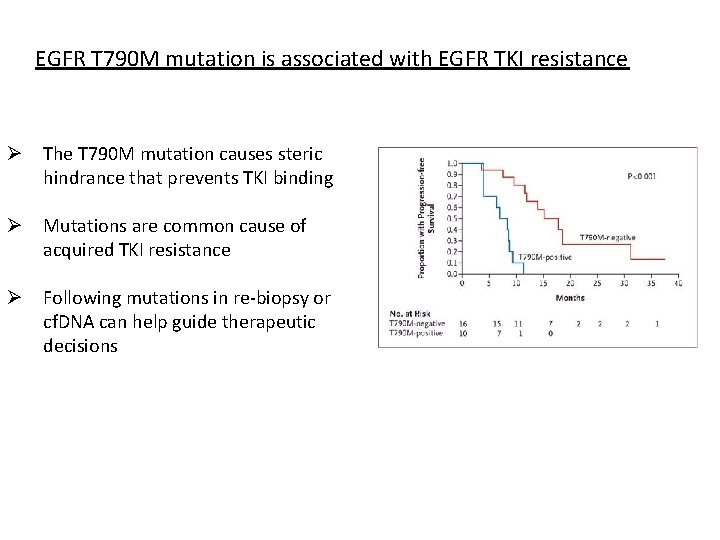

EGFR T 790 M mutation is associated with EGFR TKI resistance Ø The T 790 M mutation causes steric hindrance that prevents TKI binding Ø Mutations are common cause of acquired TKI resistance Ø Following mutations in re-biopsy or cf. DNA can help guide therapeutic decisions